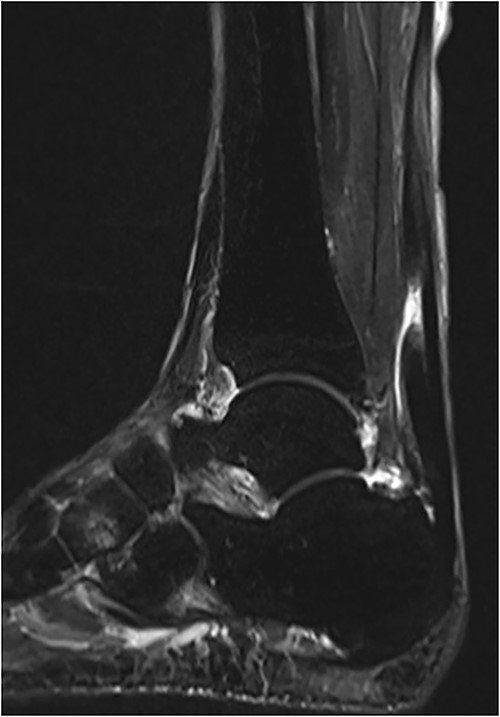

An 81-year-old male presented to a local clinic complaining of pain in his right heel without any precipitating trauma. He was diagnosed with Achilles tendinitis and treated with conservative treatment. After 2 months of conservative treatment, the patient visited our hospital because there had been no improvement in his heel pain. Physical examination revealed swelling and a palpable gap along the course of the Achilles tendon. A Thompson test was performed and proved negative, but showed reduced plantar flexion compared with the unaffected side. Plain radiographs showed no abnormal findings, whereas magnetic resonance imaging (MRI) revealed a rupture of the Achilles tendon with a gap between the tendon ends (Fig. 1). Based on physical examination and imaging findings, a diagnosis of chronic ATR was made and surgical treatment was given.